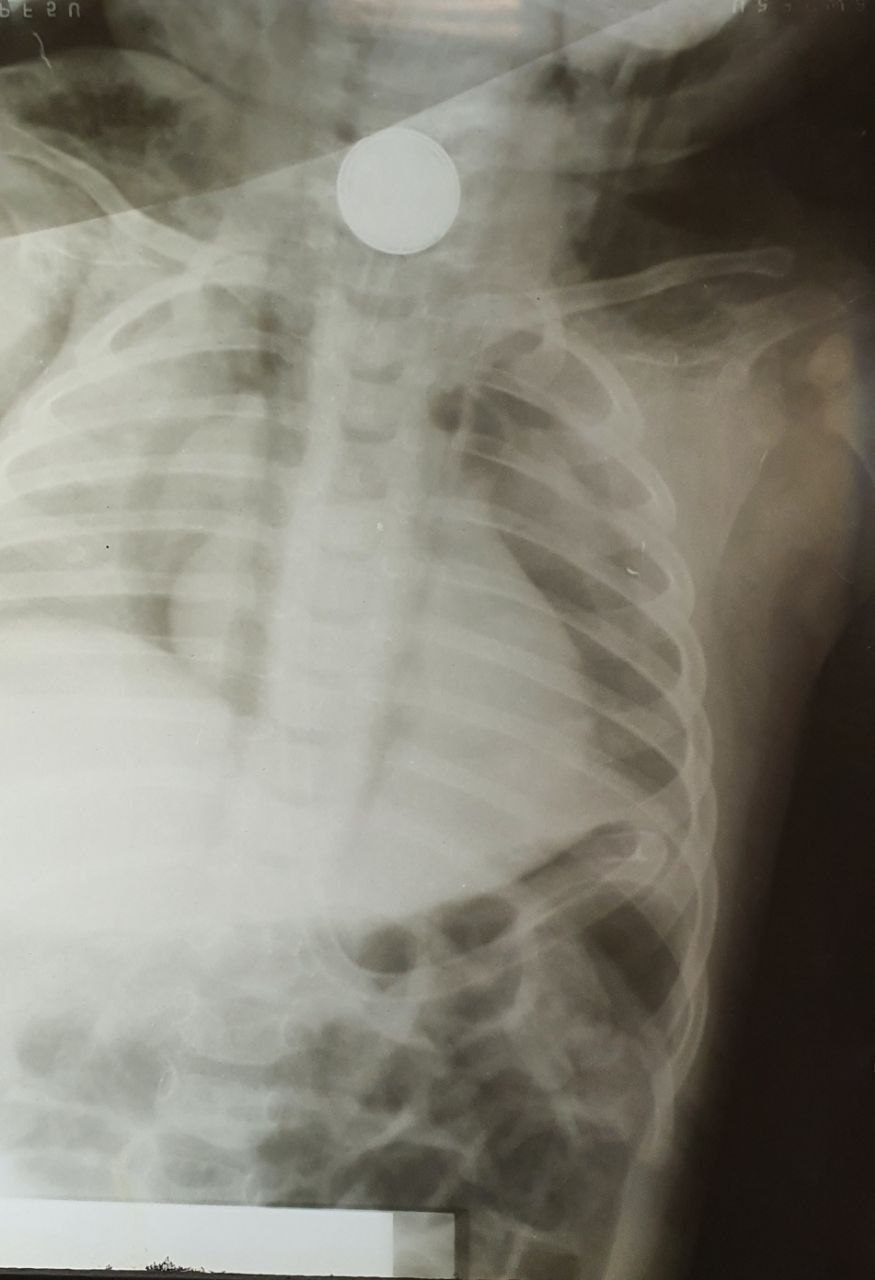

Фото ГКБ № 1